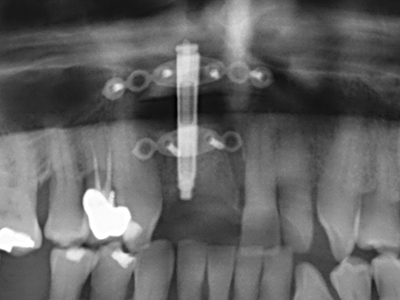

Come dimostrato in passato, pressoché qualsiasi procedura chirurgica che interessa il tessuto osseo rappresenta una possibile indicazione per la piezochirurgia. Quindi, per la preparazione del segmento mobile nella distrazione osteogenetica (figg. 23-25) e nell'osteotomia con tecnica a sandwich si utilizzano appositi raccordi per non danneggiare l'apporto sanguigno alla sezione della cresta, elemento essenziale per la corretta esecuzione di entrambe le tecniche (Gonzalez-Garcia, Diniz-Freitas et al. 2008).